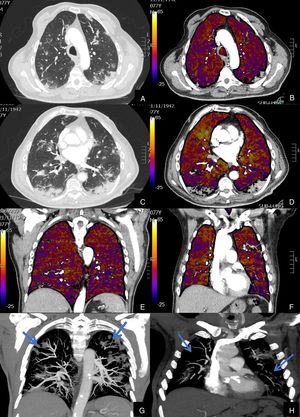

Paciente con COVID-19 con insuficiencia respiratoria grave a pesar de mejoría de parámetros inflamatorios.

Imágenes axiales de angiografía pulmonar con TC y mapa de yodo, con ventana de pulmón (A, C) en cayado y lóbulos inferiores y su correlación con las imágenes del mapa de yodo axial (B, D), coronales (E, F) y reconstrucción MIP coronal en ventana de mediastino (G, H).

Parénquima con moderada afectación parenquimatosa, con consolidaciones subpleurales parcheadas de predominio en lóbulos inferiores y extensas áreas de hipoperfusión (azules) parcheadas de predominio subpleural en el mapa de yodo, que se correlacionan con la falta de relleno del territorio vascular distal en el MIP coronal (flechas azules), sin TEP visible.